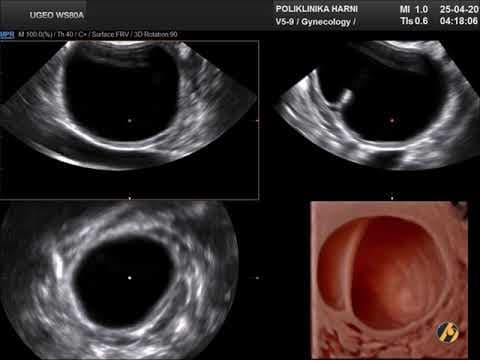

Premda su kardinalna obilježja ovog sindroma hiperandrogenizam i policističan izgled jajnika, niti jedan od pojedinačnih kriterija nije dovoljan da bi se postavila dijagnoza sindroma policističnih jajnika. Osnovna metoda u dijagnostici PCOS je ultrazvučni pregled. Koristi se transvaginalni ultrazvuk, prilikom čega se procjenjuje jesu li povećani jajnici, je li stroma - unutarnji dio jajnika koji proizvodi hormone, zadebljana, postoje li veliki broj folikula koji često tvore sliku ogrlice od perli ako su smješteni periferno ili stvaraju dojam mikrocističnosti kod difuznog rasporeda.

Dijagnoza PCOS prema Rotterdamskim kriterijima postavlja se kada žena ima najmanje dvije od sljedeće tri manifestacije: neredoviti menstrualni ciklusi ili anovulacija, povišena razina muških spolnih hormona i/ili jajnici čiji je volumen veći od 10 ml s najmanje 12 folikula na jednoj zamrznutom ultrazvučnoj slici jajnika. Nužno je isključiti ostala stanja sa sličnim znacima kao što su tumori koji stvaraju muške spolne hormone ili Cushingova bolest. Jajnici koji imaju policističan izgleda, s normalnom funkcijom i bez povišene razine muških spolnih hormona ne spadaju u sindrom policističnih jajnika i ne treba ih kao takve liječiti.